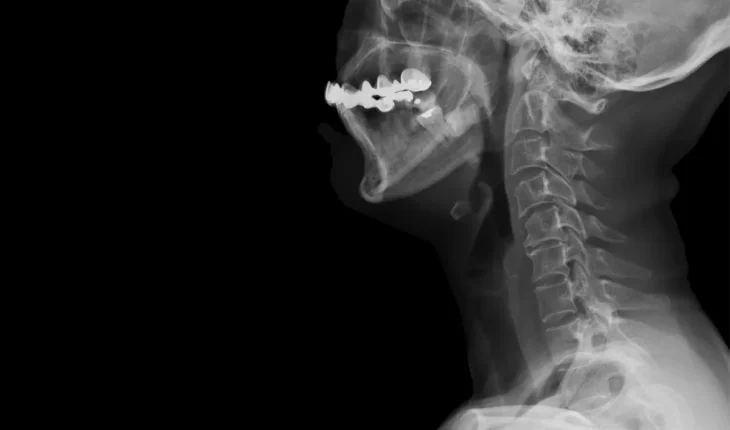

Qu’est-ce qu’une hernie cervicale ? Imaginez votre colonne vertébrale comme une pile d’assiettes. Entre chaque vertèbre, se trouvent des disques, sortes d’amortisseurs naturels. Avec le temps ou suite à un traumatisme, l’un de ces disques peut se fissurer et une partie de son noyau alors se déplace, comprimant les nerfs à proximité. C’est cette compression qui provoque les douleurs caractéristiques de la hernie cervicale.

Toutefois, si les traitements conservateurs s’avèrent insuffisants pour soulager la douleur, on recourt à traitements plus invasifs : (1) les infiltrations : Il s’agit d’injections de corticoïdes à proximité de la racine nerveuse comprimée pour réduire l’inflammation et la douleur ; (2) la chirurgie : réservée aux cas les plus graves, l’opération consiste à retirer la partie herniée du disque et à décompresser le nerf.